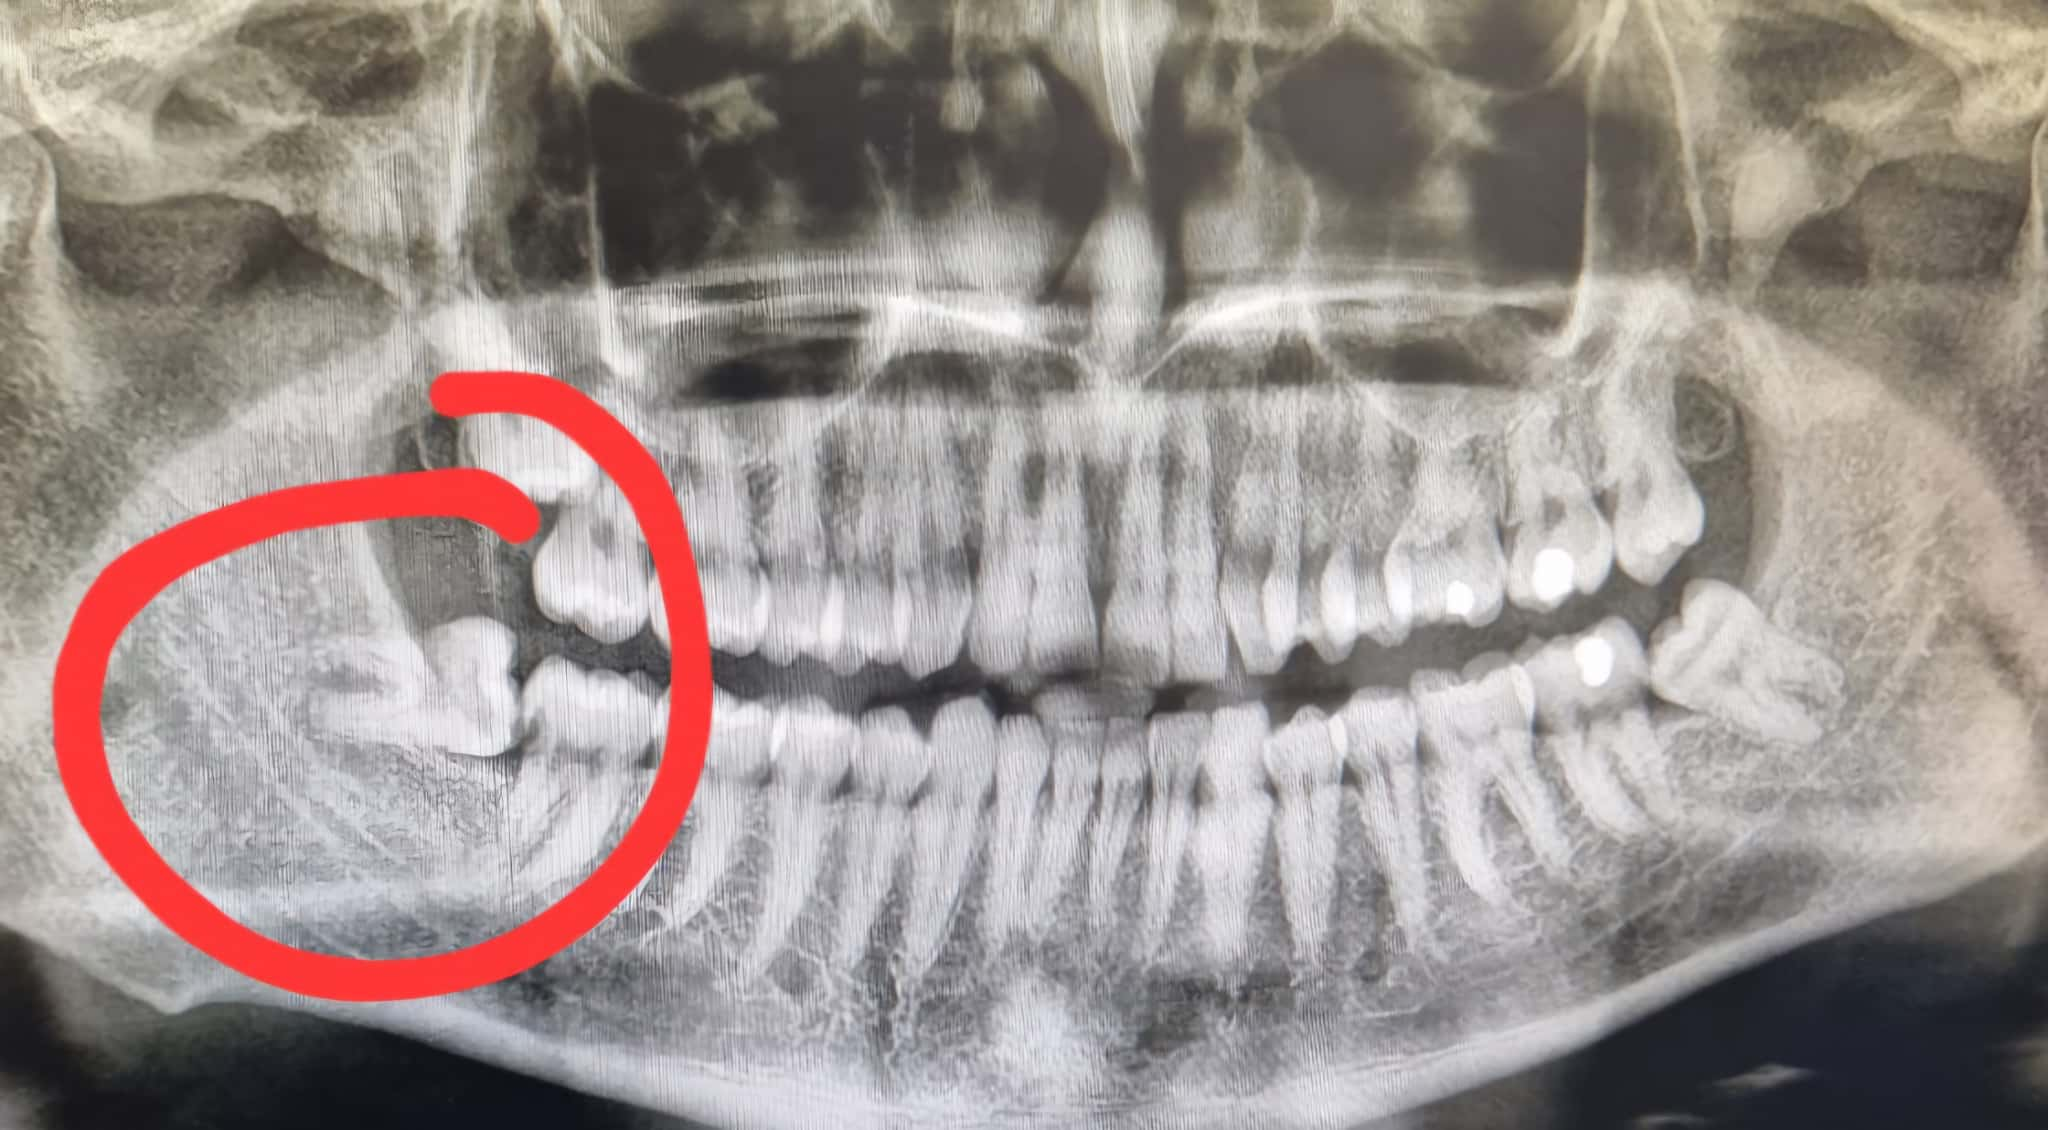

親知らずの状態は表面からはわかりにくいため、まずは歯科医院でレントゲンやCTなどの検査を受け、現在のリスクを正確に把握することが大切です。症状の有無にかかわらず、専門的な判断を仰ぐことが将来のトラブルを防ぐ第一歩となります。

最初に行うのは、親知らずの位置や向き、神経との距離を確認するための検査です。レントゲンやCT画像を使って、歯がどのように生えているのか、周囲の骨や組織とどう関係しているかを詳しく調べます。これにより、抜歯にかかる時間や難易度、リスクなどが明確になります。